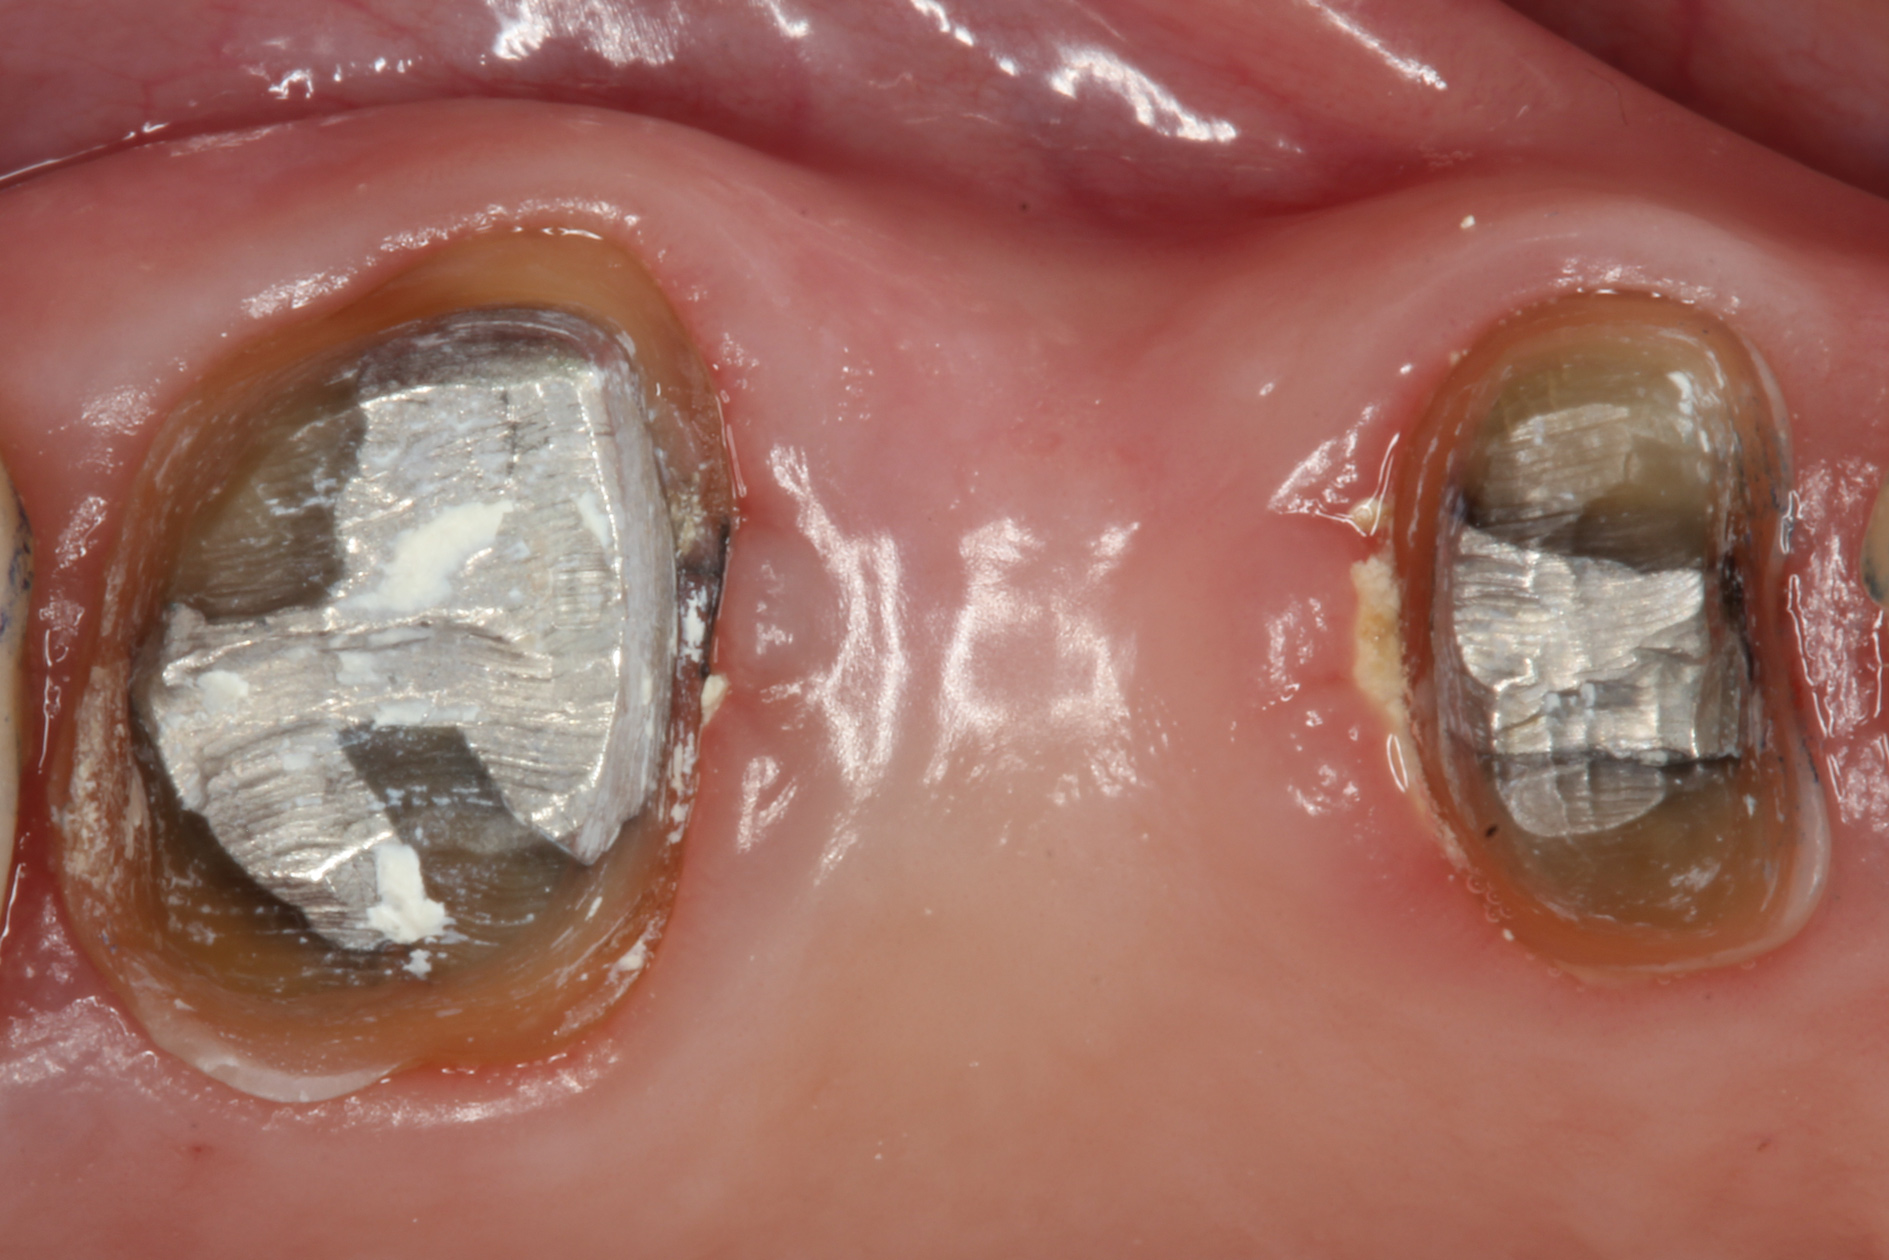

With these limitations acknowledged, visual inspection of tooth preparations after air abrasion reveals that this modality is effective in removing remnant restorative materials, stains, and temporary cement, leaving a clean, matte surface for bonding (Figure 11 through Figure 14). Air abrasion also can smooth the internal aspects of a cavity preparation to help enable better adaptation of the restorative material (Figure 15 and Figure 16). The technique-sensitive nature of adhesive bonding may justify this extra procedure to ensure a clean, smooth preparation.

Fig 13. Crown preparations with temporary cement remnants prior to air abrasion (Fig 13) and after air abrasion (Fig 14) (case by Mohammed Badahman, DDS).

Figure 13

Fig 14. Crown preparations with temporary cement remnants prior to air abrasion (Fig 13) and after air abrasion (Fig 14) (case by Mohammed Badahman, DDS).